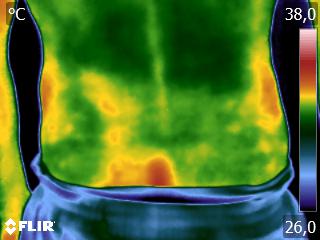

Como no caso do termograma abaixo de um paciente do sexo masculino, 52 anos, sem comorbidades e que apresenta dor em ombro após treino de musculação. Foi realizado uma Análise Termofuncional e detectado alterações térmicas condizentes com o relato de dor.

Segundo os conhecimentos da Termofuncional, estes resultados representam sobrecarga tecidual, podendo estar ligada a biomecânica errada. Através destes conhecimentos é possível o terapeuta partir para uma análise focada na biomecânica e na carga de treinamento, corrigindo ambas.

Além, claro, de permitir um mapa para escolhas de tratamento através de métodos e técnicas terapêuticas que o profissional achar adequado. Ao longo da reabilitação, também é possível o profissional monitorar os resultados alcançados para aumento da eficácia do tratamento.

Tudo isso também permite o registro documental que é a sua segurança e a do paciente. Nenhuma outra técnica permite, de forma autônoma, um registro documental tão preciso como este.